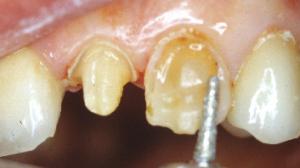

Dans le cas d'une canine, il faut englober la concavité. La fraise boule réunit en palatin les congés proximaux en traçant un sillon palatin apicalement au contact occlusal. Le bord libre sera diminué de 1 mm.

Le contact occlusal se fera sur la céramique. Un espace de 1 mm a été ménagé entre la préparation et la dent antagoniste avec la fraise boule.

Un premier fil rétracteur fin est inséré. Il écarte légèrement la gencive.

Nous descendons la limite cervicale jusqu’à " effleurer " le fil sans toucher la gencive avec la fraise.

A aucun moment de la préparation la fraise ne doit toucher la gencive !

Les limites de préparation sont actuellement juxta-gingivales.